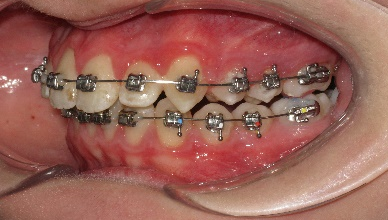

В последующем, после дистализации моляров на верхней челюсти, аппарат снят и на втором этапе ортодонтического лечения фиксирована брекет-система пассивного самолигирования NexStep Pro с пазом 0.22 (стандарт). Уникальная конструкция замка-слайда обеспечивает повышенный контроль торка и ротации, а прецизионность паза брекета дает полную реализацию программы, заложенную в брекетах данной системы SLS. (рис.6 )

На завершении проведения этапа нивелирования начинается активная дистализация первых и вторых премоляров на верхней челюсти с помощью открывающих пружин, выполненных из сплава NiTi c незначительной силовой нагрузкой. (рис.7.)

Рис.7. Этап нивелирования на аппарате NexStep Pro 0.22

После дистализации боковых сегментов на верхней челюсти и правильной постановки клыков в зубной ряд проведена фиксация аппарата на нижний зубной ряд и дальнейшая коррекция окклюзии проводится по стандартному протоколу, т.е. нормализация формы зубных рядов на верхней и нижней челюсти с правильной постановкой зубов по торку в боковых и во фронтальном отделах, что дает реализация программы, заложенная в пассивной самолигирующей брекет- системе NexStep Pro 0.22. (рис.8)

Рис.8. Этап контроля торка на верхней челюсти и фиксация аппарата на нижней челюсти для проведения этапа нивелирования.